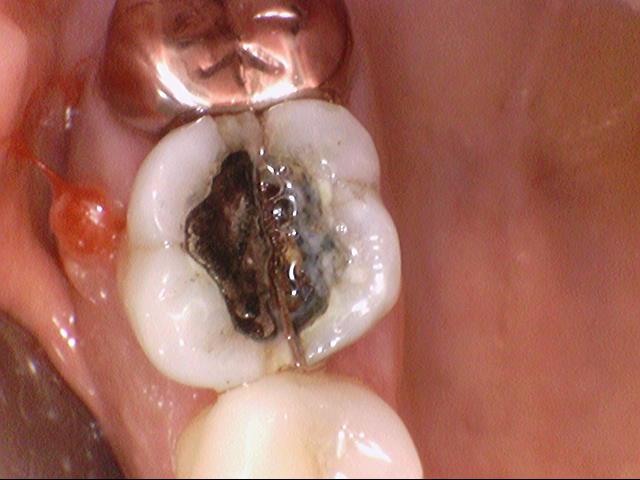

또한 기존에 아말감치료를 오래전에 했다가

치아색으로 교체를 원하는 경우 보통 아말감치료는 크기가 큰 경우가 많아서

레진보다는 세라믹인레이로 진행하게 되고

아주 크기가 큰 경우 또는 아말감 주위로 광범위하게 충치가 있는경우는 크라운으로 진행하게 되기도 합니다.

기존 오래된 아말감을 치아색깔이 나는 세라믹 인레이로 교체